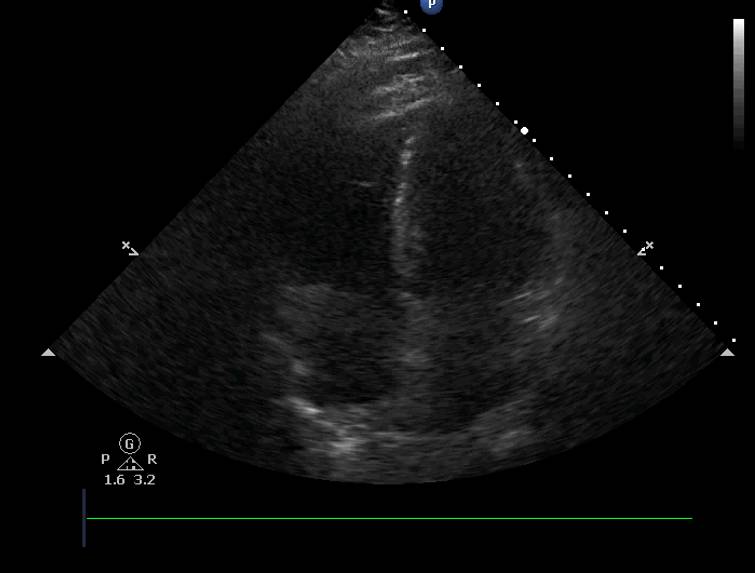

心脏彩超

右:左=1:1

IVC>2.5cm

EF:0.35